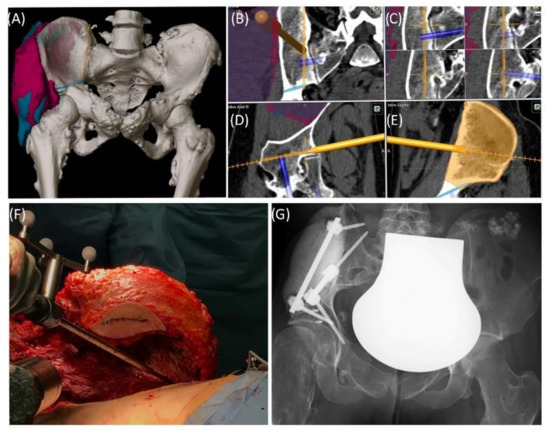

A 59-year-old female patient was diagnosed with bone metastasis of endometrial carcinoma of the sacrum with increasing and immobilizing pain. Primary radiation was discussed, but primary surgery and adjuvant radiation were preferred. Preoperatively, bladder/rectum dysfunction and a bladder-vaginal fistula were already present due to significant metastatic progression. The goal of 3D model-based planning and navigation was marginal resection of the metastasis in terms of a partial sacrectomy below S2 with ligation of the dural tube and the descending nerve roots below S2 (Figure 3 and Figure 4). Repeated revision surgery and systemic antibiotic treatment after wound infection were necessary. At the two-month follow-up, further metastases with pulmonary foci, which did not exist preoperatively, were found. Palliative treatment and radiation followed.

Figure 3. Case 2: Tumor segmentation (A) and resection plane planning (B), as well as preoperative validation of model accuracy with a navigated chisel resection of the 3D-printed model (BE).

Figure 4. Case 2: 3D model of navigated chisel resection (A); resection planes in the axial and transversal planes (C,D); intraoperative view of the navigated chisel with crosshairs showing the location of the tip (B).